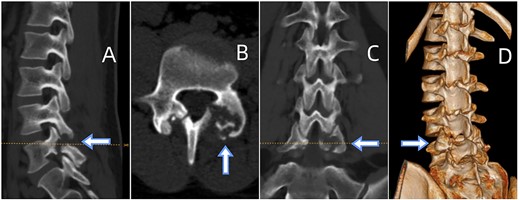

CT showed erosions in the facet joints over left L5-S1, with soft tissue masses and sclerotic margins (Fig. 1). MRI depicted a 1.8◊1.1 cm extra-dural mass in the left L5-S1 facet joints, displaying low signal on T1-weighted and high signal on T2-weighted imaging. Gadolinium contrast highlighted heterogeneous enhancement of the lesion (Fig. 2).

(A) Sagittal CT displaying lumbar spondylolysis at L5. (B) Axial CT revealing articular subchondral erosions and soft tissue masses at the left facet joint L5-S1. (C) Coronal CT and (D) 3D image demonstrating articular erosions and punched-out lesions of L5-S1, along with spondylolysis at L5.